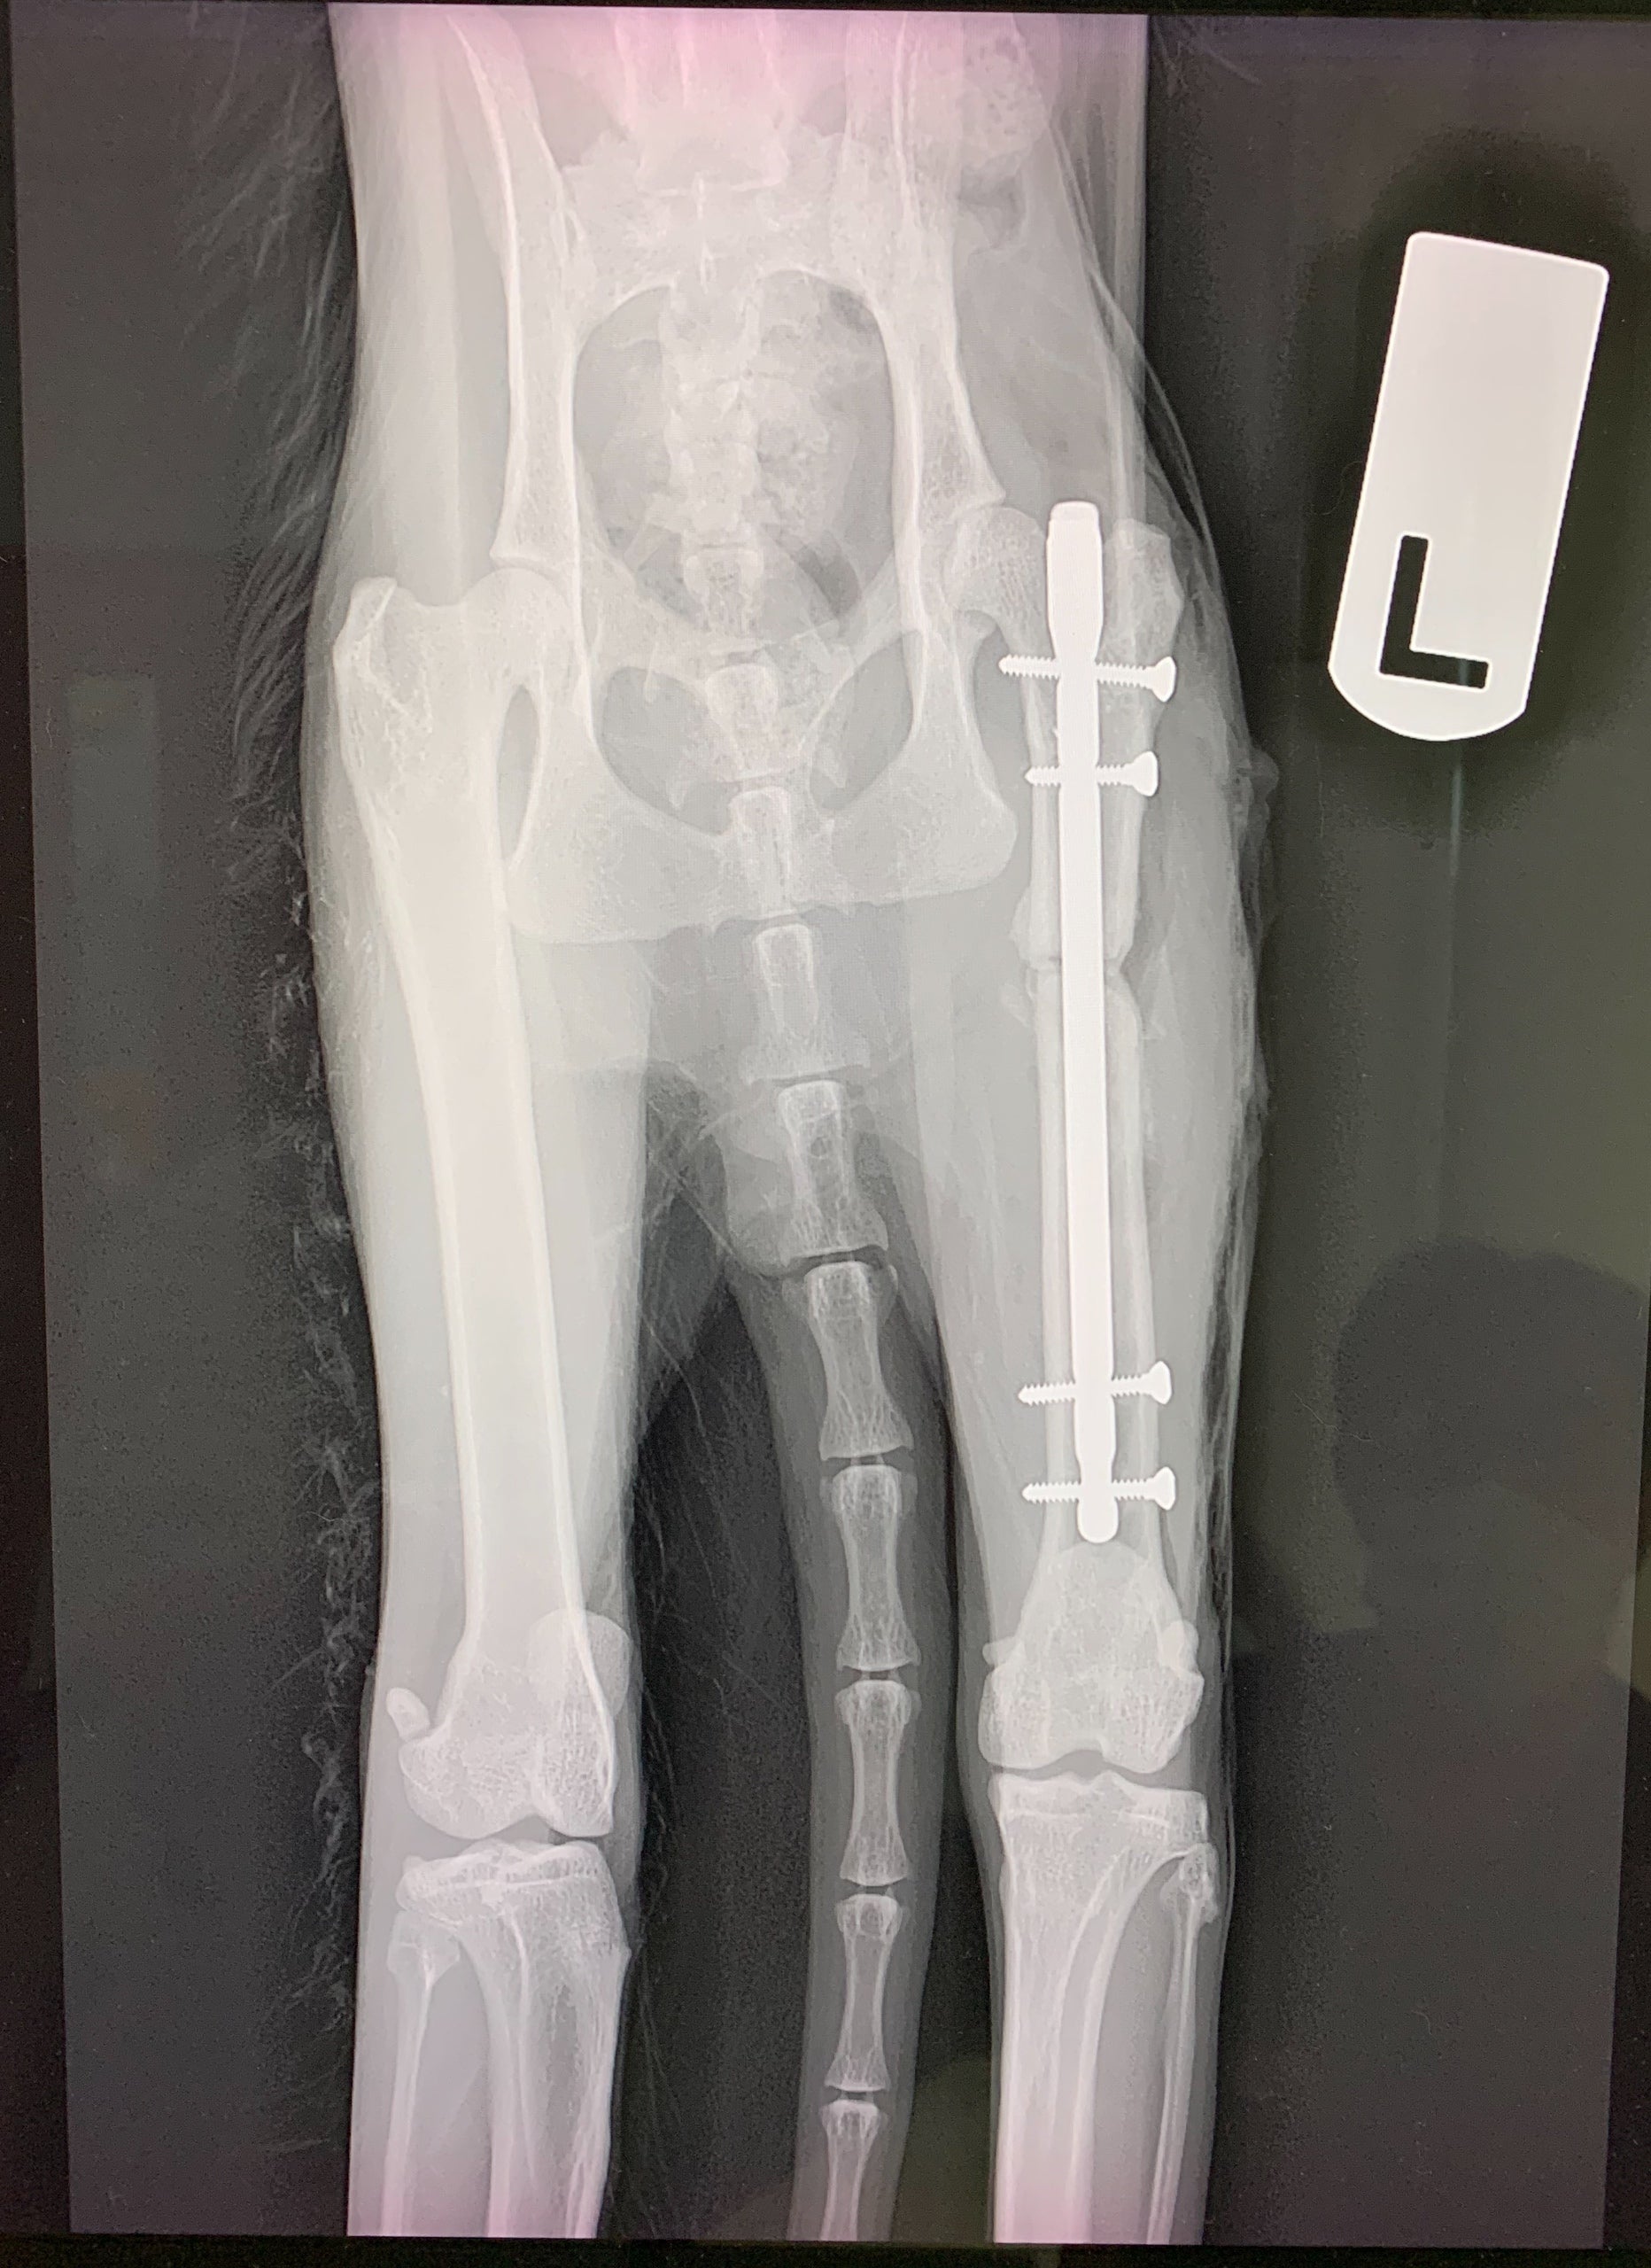

最短の日程で、手術は実施する運びとなりましたが、『まめおくん』は極度の貧血状態で、直ぐには手術することができませんでした。幸い1匹の猫ちゃんから輸血を受けることができ、8月30日の夜、手術開始となりました。大腿骨の一部切断、離れた骨をインプラントにより固定するという大手術でした。

手術は無事成功し、定期的なレントゲンによる経過観察を行っていくことになりました。